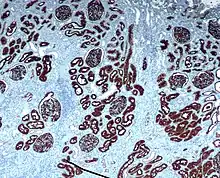

Immunohistochemistry (IHC) is the most common application of immunostaining. It involves the process of selectively identifying antigens (proteins) in cells of a tissue section by exploiting the principle of antibodies binding specifically to antigens in biological tissues.[1] IHC takes its name from the roots "immuno", in reference to antibodies used in the procedure, and "histo", meaning tissue (compare to immunocytochemistry). Albert Coons conceptualized and first implemented the procedure in 1941.[2]

- Chromogenic immunohistochemistry (CIH), wherein an antibody is conjugated to an enzyme, such as peroxidase (the combination being termed immunoperoxidase), that can catalyse a colour-producing reaction.[3]

Immunohistochemical staining is widely used in the diagnosis of abnormal cells such as those found in cancerous tumors. Specific molecular markers are characteristic of particular cellular events such as proliferation or cell death (apoptosis).[4] Immunohistochemistry is also widely used in basic research to understand the distribution and localization of biomarkers and differentially expressed proteins in different parts of a biological tissue.

Reporter molecules vary based on the nature of the detection method, the most popular being chromogenic and fluorescence detection mediated by an enzyme or a fluorophore, respectively. With chromogenic reporters, an enzyme label reacts with a substrate to yield an intensely colored product that can be analyzed with an ordinary light microscope. While the list of enzyme substrates is extensive, alkaline phosphatase (AP) and horseradish peroxidase (HRP) are the two enzymes used most extensively as labels for protein detection. An array of chromogenic, fluorogenic and chemiluminescent substrates is available for use with either enzyme, including DAB or BCIP/NBT, which produce a brown or purple staining, respectively, wherever the enzymes are bound. Reaction with DAB can be enhanced using nickel,[9] producing a deep purple/black staining.